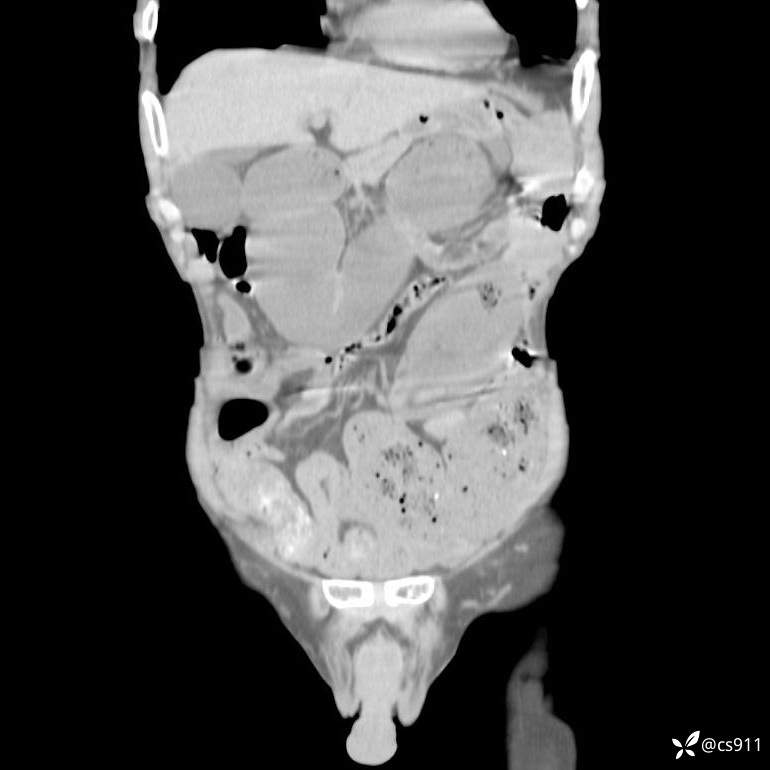

急腹症之急诊CT,原因?答案公布

男,77岁,腹痛、腹胀伴恶心呕吐1天。呕吐胃内容物,非喷射性呕吐,有咖啡色样胃内容物,诉有胃穿孔病史。查体:全腹平,下腹部压痛,全腹无反跳痛,叩诊呈浊音,移动性浊音阴性,肠鸣音减弱,1-2次/分。肛检:直肠未扪及明显肿物,可触及大量粪块。

T 36.6℃ P 80次/分 R 26次/分 BP 100/60mmHg

白细胞(WBC) H 14.55 10e9/L 4-10

中性粒细胞百分率(NEUT%) H 85.7 % 40-75

血淀粉酶(AMY) HH 1859 U/L 35-135

癌胚抗原(CEA) H 27.44 ng/ml 0-5

呕吐物 潜血试验 * 阳性 阴性

患者轮椅入室检查神志清楚, 能配合摆位和呼吸